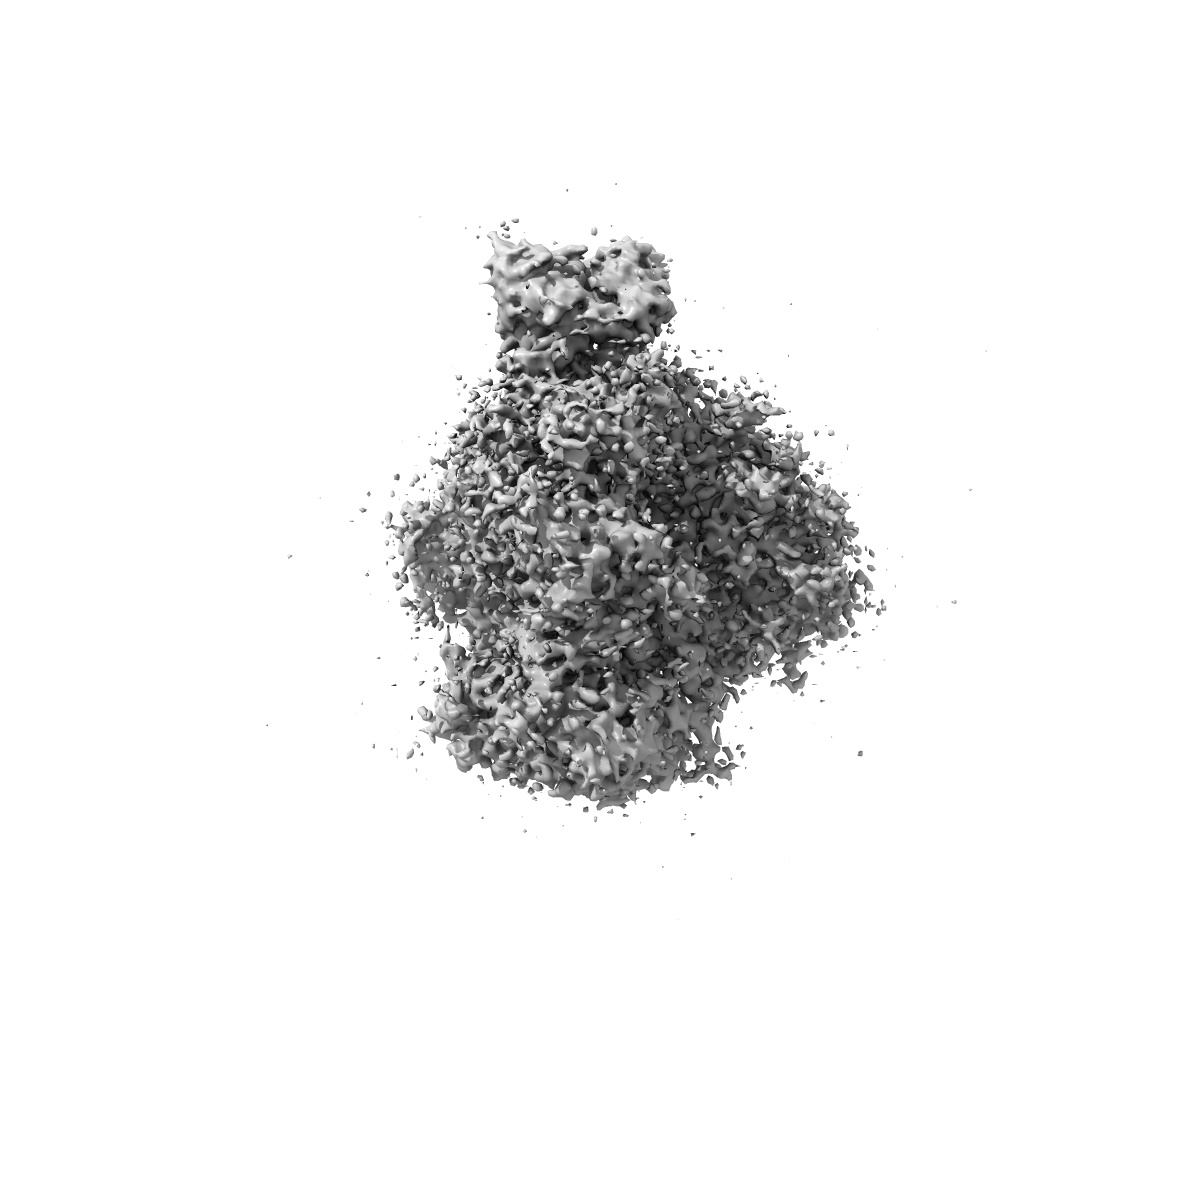

Cryo-EM Structure of PG9RSH DU025 Fab in complex with BG505 DS-SOSIP.664

Single-particle

3.75 Å

Sample: Cryo-EM Structure of PG9RSH DU025 Fab in complex with BG505 DS-SOSIP.664

Fitted models: 8fl1

Improved HIV-1 neutralization breadth and potency of V2-apex antibodies by in silico design.